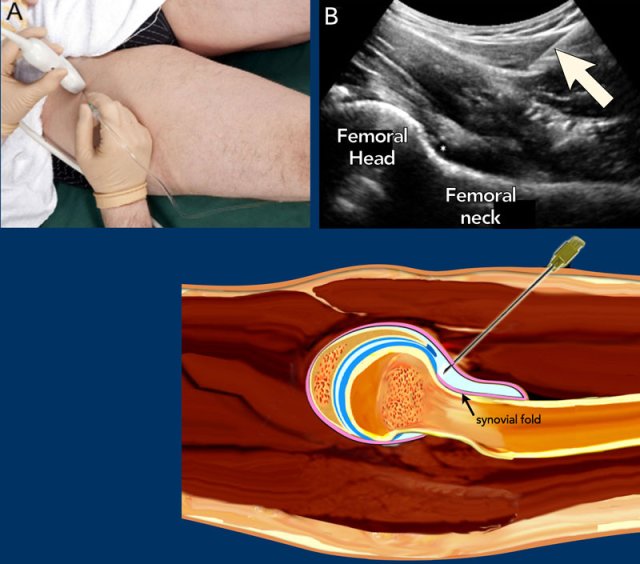

The patient is placed supine. The leg is held in slight endorotation and abduction thereby reducing tension on the capsular structures and moving the iliopsoas tendon and bursa medially out of the intended needle path.

Preferably a 5-3.5 MHz curved array transducer is used, which provides the necessary penetration depth.

Usually a 21 gauge needle with a length of 9 cm is used for the average adult. In smaller adults or children a 23-gauge, 5 cm hypodermic needle might be used.

Local anaesthetic may be injected prior to the main injection but this entails extra manipulation as well as non-contrast fluid (anaesthetic) in the joint leaving less room for the contrast in the limited joint space as well as possibly 2 punctures.

The needle may inadvertently be withdrawn from the joint after anaesthetic injection during the switch to connect the syringe with contrast. This could be avoided by using a three-way connector between the two syringes containing the anaesthetic and the injection fluid (contrast or medication).

The needle is advanced at a caudo-cranial angle along the long axis of the transducer aiming for the anterior recess near the junction of the femoral neck with the femoral head (see US and illustration).

The bevel of the needle should be facing toward the joint.

When the needle makes contact with the femoral head-neck junction it is slightly retracted to prevent inadvertently injection underneath the synovial fold of the hip joint capsule (see drawing).

If correctly positioned within the joint capsule, 10-15 mL contrast media or medication is injected and the anterior recess will distend by the injected fluid confirming the intra-articular positioning.